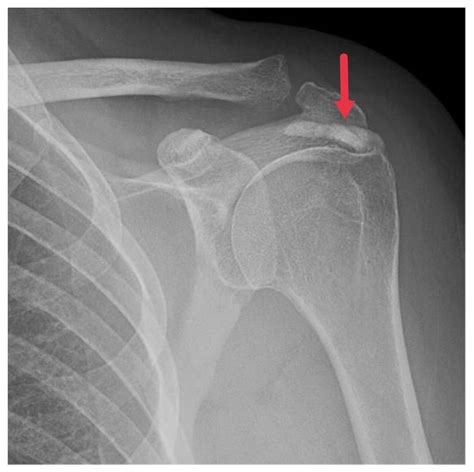

HADD can affect various joints, including the shoulder, elbow, wrist, hip, knee, and ankle. It can also occur in soft tissues such as tendons and ligaments. The most commonly affected areas are the shoulder and the wrist.

• Imaging Studies: X-rays, ultrasound, and magnetic resonance imaging (MRI) can help identify the presence of hydroxyapatite crystals and assess the extent of the deposits.

Imaging studies are particularly important in diagnosing HADD. X-rays can show calcifications in the affected areas, while ultrasound and MRI provide more detailed images of the soft tissues and joints. Laboratory tests can help rule out other conditions that may cause similar symptoms.